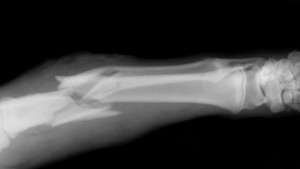

However, because the disease is virtually symptomless it can mean that it goes completely undiagnosed. That is until the point that you suffer a very painful bone fracture usually at the hip or the wrist. But there is good news, as emerging studies are indicating that tocotrienols can help strengthen brittle bones.

Fractures are the most dangerous part of having osteoporosis. It’s not just the initial damage that they cause; it’s the lasting, chronic pain that can actually lead to disability in elderly people. Once you have an osteoporotic fracture you are likely to develop another. That’s why this new information is so interesting and so promising for the future of treating the problem.